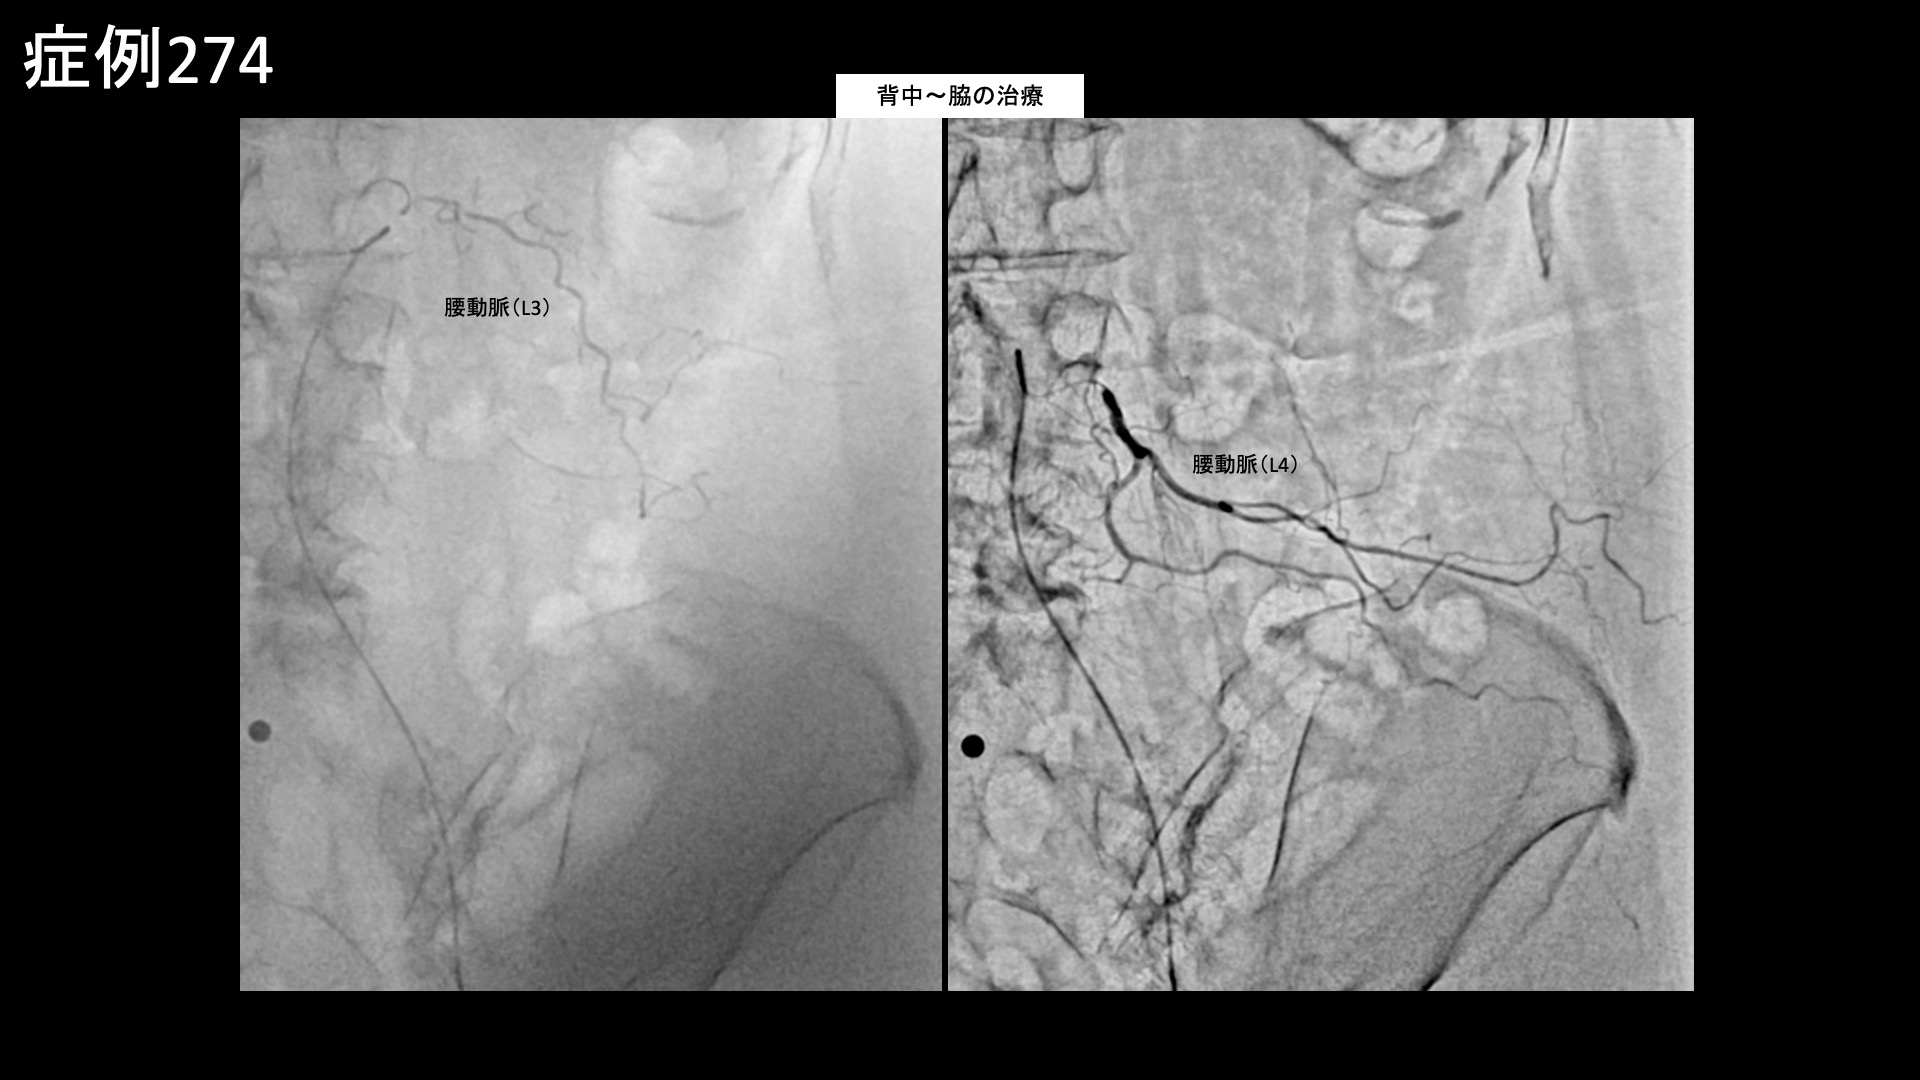

その他:帯状疱疹後など 【70代:女性】それほど目立たない発疹だったのにこんなに痛くなるなんて・・下腹部、脇腹に生じた発症1ヶ月半の帯状疱疹後神経痛 2026.03.27 鴨井院長による動画解説 受診までの経過 11ヶ月前から左肩が痛むようになり、整形外科や鍼灸院など複数の施設に通いました。3ヶ月くらいで治ると言われ、注射治療などを受けましたが、半年くらいでようやく少しおさまったものの腕はいっこうに上がりませんでした。それどころか右肩も痛くなり、夜間痛や起床時痛にも見舞われ、朝から気力を奪われてしまい、洗髪・洗顔など日常生活にも大きく支障をきたすようになりました。元々は毎日出かけたい性分でしたが、最近はどこにも行きたくなくなってしまうほどでした。 診察時の所見 発症1ヶ月半の帯状疱疹後神経痛であり、その他特段の治療抵抗要因(投薬治療を要する鬱の合併、極端な体重減少や『るいそう』、極端な活動性の低下や社会/家族との断絶、破局的思考、高度の貧血その他)は見られないことから治療による改善が見込まれました。治療適応と判断し、モヤモヤ血管(病的新生血管)に対する運動器カテーテル治療(微細動脈塞栓術)を受けていただきました。 治療の所見 下腹部の主要責任血管である下腹壁動脈、脇腹の主要責任血管である深/浅腸骨回旋動脈、さらに背中~脇腹に分布する腰動脈を順に治療しました。それぞれ一定の再現痛を確認しました。その他複数個所の治療を行い終了しました。 *再現痛とは、薬液投与時に普段の痛みが一定程度再現される現象です。責任血管の同定のための参考とします。 治療後の経過 治療後2週間で寝られるようになりました。背中の痛みはあまり感じなくなりました。治療後1ヶ月半、7-8割程度の痛みは改善しました。鎮痛薬を服用する頻度も減りました。治療後3ヶ月、痛みはほぼ消失しました。ゼロではないものの違和感程度になりました。腹部の痛みは治りにくいと聞いていたので、早く治療を受けて良かったと言われました。 当初の発疹はそれほど激しくはありませんでしたが、特に腹部の症状は強く感じていました。下腹部や脇腹は比較的敏感な部位であり、激しい発疹でなくても強くしつこい嫌な痛みが持続しやすいです。腹部は比較的治りにくい部位ですので、治療を決断されて良かったと思います。高齢になるほど回復に時間を要する傾向がありますが、早期に治療を受けていただいたことが早い回復につながったものと思われます。帯状疱疹後神経痛は難治の痛みの一つであり、その臨床経過にも様々なパターンがあります。今回は腹部の症状について取り上げました。ご参考にしていただければ幸いです。 帯状疱疹後神経痛の詳細はこちら 【30代:男性】マラソンランナーに生じた大腿裏付け根の痛み、ハムストリングス付着部炎に対するモヤモヤ血管治療(ハムストリングス付着部炎、仙腸関節障害) 前の記事 【40代:女性】常に陰部が腫れぼったく、下着が擦れるだけでもヒリヒリして座っていられない・・日常生活を完全に破壊されてしまった、新型コロナウイルス(Covid-19)に併発した発症3ヶ月の間質性膀胱炎および誘発性膣前庭炎に対するモヤモヤ血管治療(間質性膀胱炎、誘発性膣前庭炎、新型コロナウイルス(Covid-19))、Long COVID) 次の記事